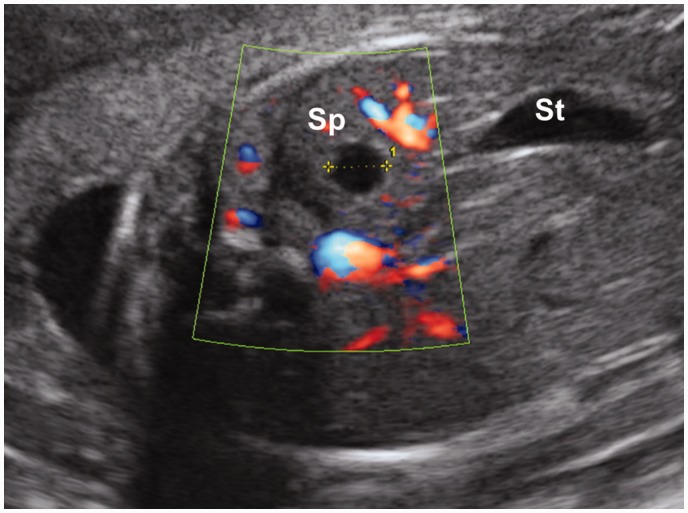

基因检测单位名称:江西省萍乡市基因检测应用中心。现有病例 32 例,共新增 9 例。 在脾脏囊肿基因检测的所有病例中,除了一个病例,脾囊肿的产前检测是在妊娠晚期进行的,诊断时的中位孕龄为 30 周(范围 22-37)。 除 1 例失访外,均在分娩后确诊为脾囊肿。 其余 8 例产后超声检查显示,2 例 (25%) 囊肿增大,1 例 (12%) 大小稳定,1 例 (12%) 囊肿缩小,1 例完全消退 四例(50%)。 婴儿中没有与囊肿相关的并发症的报道。其他成熟基因检测项目:疫苗特异性抗体反应降低肿瘤基因检测, 3-甲基戊二酸尿症基因体检

脾囊肿基因检测方法: 来自甘肃省天水市麦积区马跑泉镇的温凯新(化名)在孝感市(中心)人民医院被医生诊断为脾囊肿。学习《Gastric Cancer》,脾囊肿的出现有多种原因,其中一个重要的原因是基因突变。通过全外显子测序、全基因组测序,结合基因解码,基本上建立了基因突变与疾病发病的因果关系,而且佳学基因在多个人群重复出了结果,其他研究机构还在分子、细胞及动物实验中验证了这些结果。通过基因检测可以验证或排除疾病发生的基因原因,从而阻断遗传,降低对生活带来的精神和生理上的痛苦。

A closed sac located in the spleen.